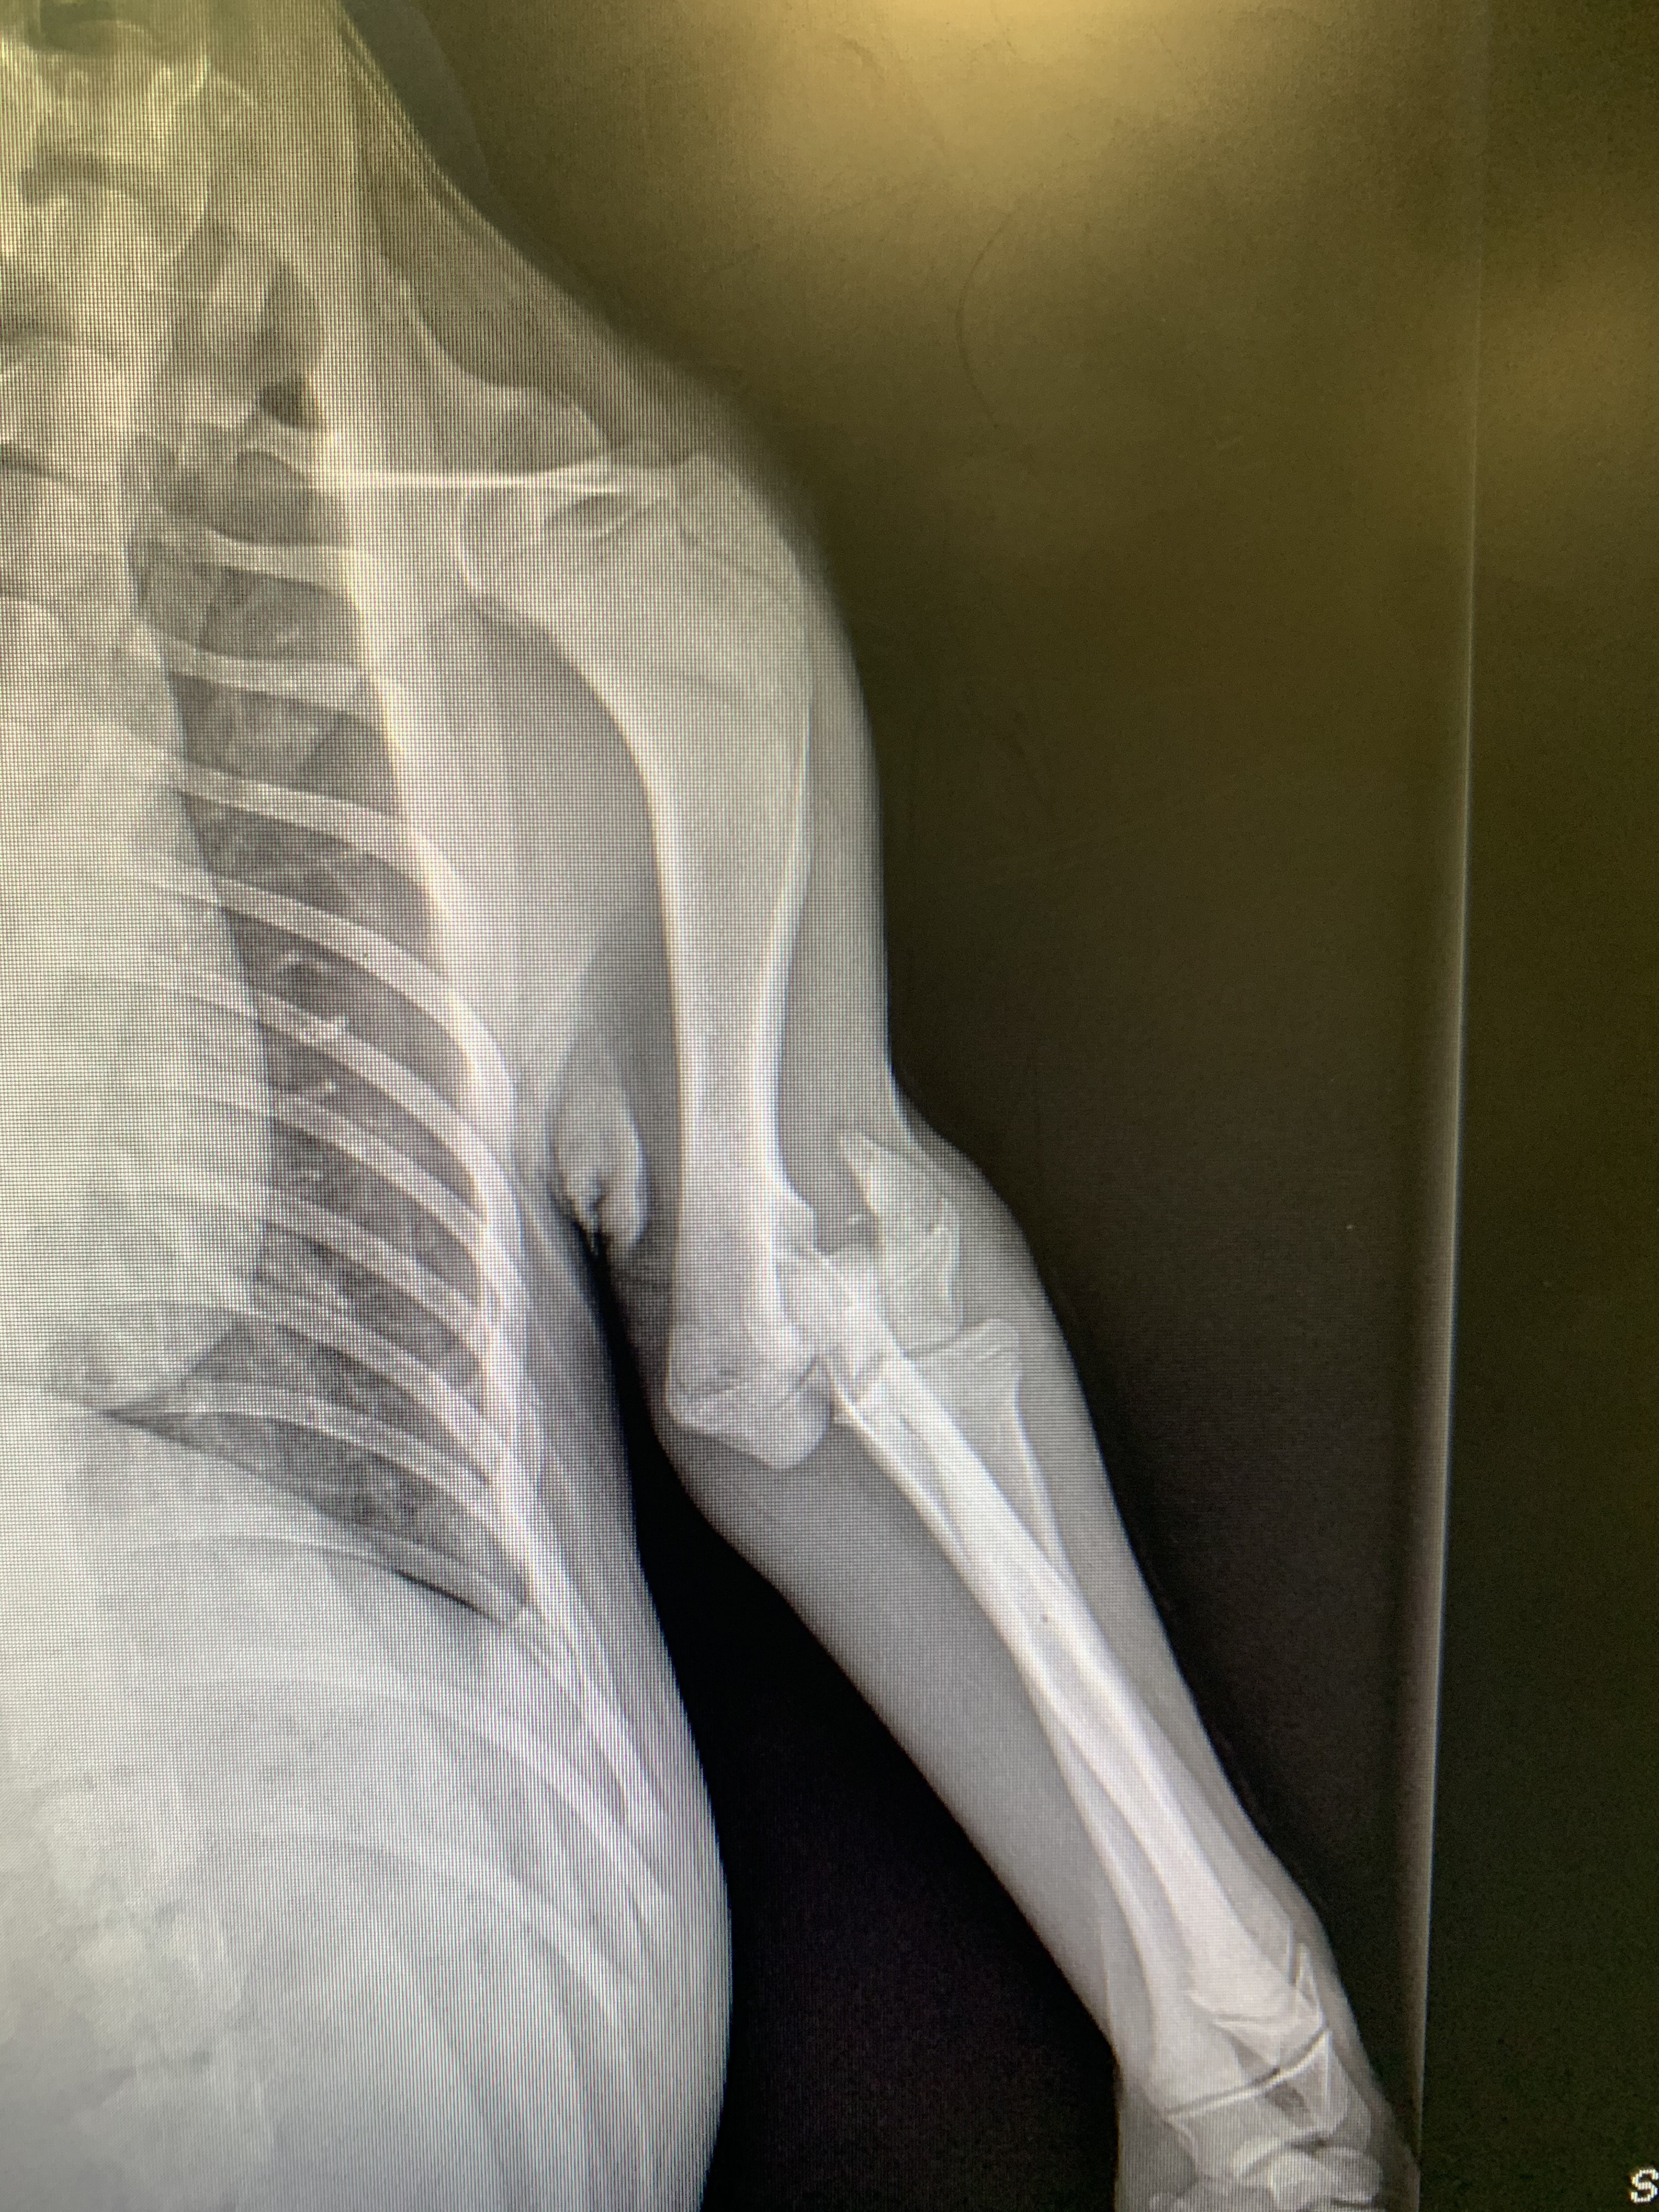

She had no identifying marks and seems to have been feral for most or all of her 4 month life. She was in bad shape and had fleas, ticks, intestinal issues, and a badly broken elbow.

The vet took her to their ranch for the amputation and to make sure she’s healthy. She joined us last Friday. She took to Colin right away and has slowly agreed that the rest of us might be ok too.